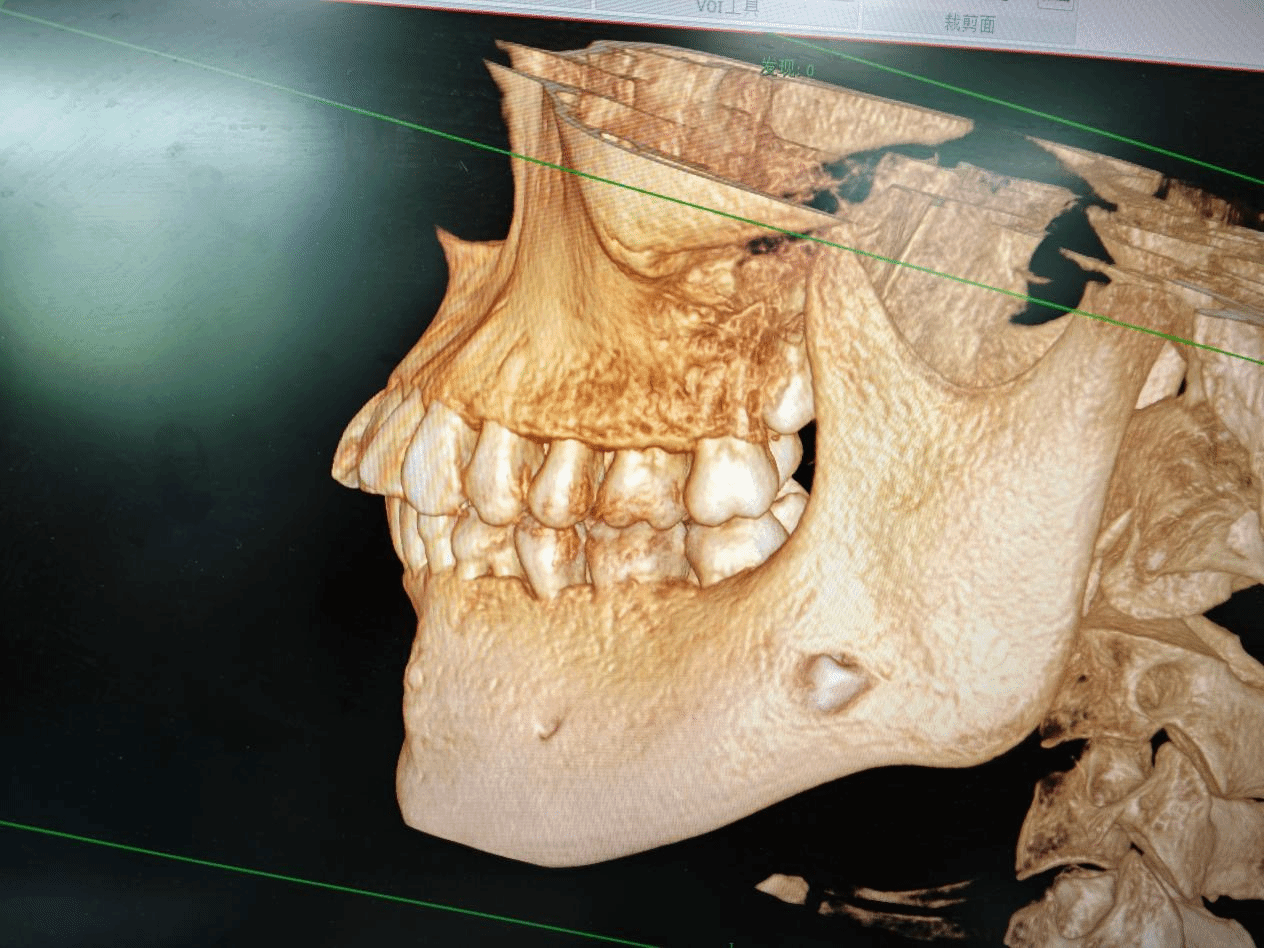

今年13岁的小海(化名)因牙齿不整齐来我院牙颌颜面发育管理中心就诊,希望通过正畸能排齐牙齿,在检查中发现他有两颗乳牙滞留,经过进一步影像学检查,揭示了他下颌骨内有牙瘤及异位埋伏阻生牙。牙瘤的出现通常伴随骨质膨隆或牙齿缺失,而异位的埋伏阻生牙则可能影响恒牙的正常萌出,因情况复杂,小海随即转至我院头颈肿瘤科接受进一步治疗。

在全面评估小海的情况后,头颈肿瘤科团队决定实施手术,手术需要医生们细致操作,确保完整摘除牙瘤组织,同时避免损伤上方牙根及周围神经,异位的埋伏阻生牙位于下颌骨关键区域,拔除过程需极其小心,避免损伤神经和恒牙胚。一切准备就绪后,手术在全麻下进行,成功摘除了形态各异的牙样组织,并完整拔除了埋伏阻生的两颗牙齿。术后小海恢复良好,未出现并发症。